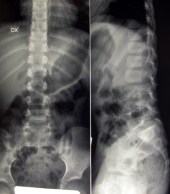

La lisi, spesso asintomatica, si localizza quasi sempre nel tratto lombare inferiore (in particolare IV e V vertebra lombare) ed è più frequente di quanto si creda, realizzandosi per il concorrere di fattori ereditari congeniti (displasia dell’istmo) o meccanici (microtraumi in iperestensione in soggetti con iperlordosi lombare). Il viraggio sintomatologico (lombalgia) si verifica in età scolare o più spesso adolescenziale. La diagnosi è radiografica: oltre alle proiezioni antero-posteriore e latero-laterale, sono necessarie le proiezioni oblique che mostreranno l’immagine tipica del cagnolino con una interruzione (lisi) a livello del collo (fig 3). Una volta fatta la diagnosi, bisognerà consigliare le stesse norme comportamentali valide per l’iperlordosi lombare, senza precludere al bambino la possibilità di praticare attività sportive, ma sconsigliando quelle (come la ginnastica artistica, il judo, il salto in alto, il nuoto stile delfino, il surf, etc.) che comportano un forte lavoro in iperestensione del rachide lombare.